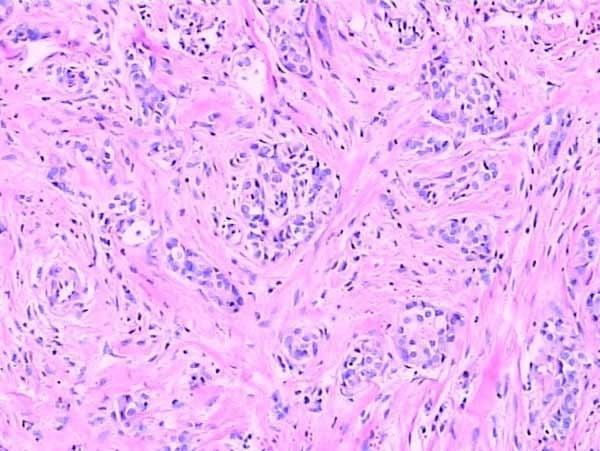

石蠟切片

此外,在染色性能方面,兩種切片技術(shù)也各有千秋。石蠟切片適用于多種染色技術(shù),如H&E染色等,能夠清晰地展示組織的細(xì)胞結(jié)構(gòu)和形態(tài)。而冰凍切片則更多地應(yīng)用于免疫組化和原位雜交等特殊染色技術(shù),為科研人員提供了更多維度的觀察手段。